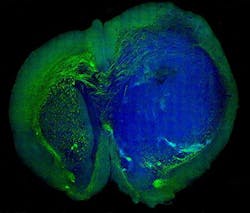

They used the SRS microscopy technique to distinguish tumor from healthy tissue in the brains of living mice—and then showed that the same was possible in tissue removed from a patient with glioblastoma multiforme, one of the most deadly brain tumors.

The work marks the first time that SRS microscopy has been used in a living organism to see the "margin" of a tumor (the boundary area where tumor cells infiltrate among normal cells), which is the hardest area for a surgeon to operate—especially when a tumor has invaded a region with an important function. The technique can distinguish brain tumor from normal tissue with remarkable accuracy by detecting the difference between the signal given off by the dense cellular structure of tumor tissue, and the normal, healthy gray and white matter. Better still, the authors suggest that SRS microscopy may be as accurate for detecting tumor as the current H&E staining approach used in brain tumor diagnosis.The paper contains data from a test that pitted H&E staining directly against SRS microscopy. Three surgical pathologists, trained in studying brain tissue and spotting tumor cells, had nearly the same level of accuracy, no matter which images they studied. But unlike H&E staining, SRS microscopy can be done in real time, and without dyeing, removing, or processing the tissue.